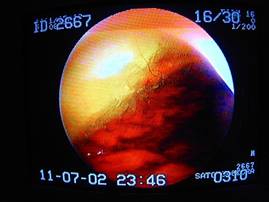

クルッと回転して、胃の入り口をチェック

(噴門部を確認)

がっちりと鉗子で捕まえ、摘出中。

取り出した異物はこれ。

これは詰まってしまう可能性が充分ありますね。